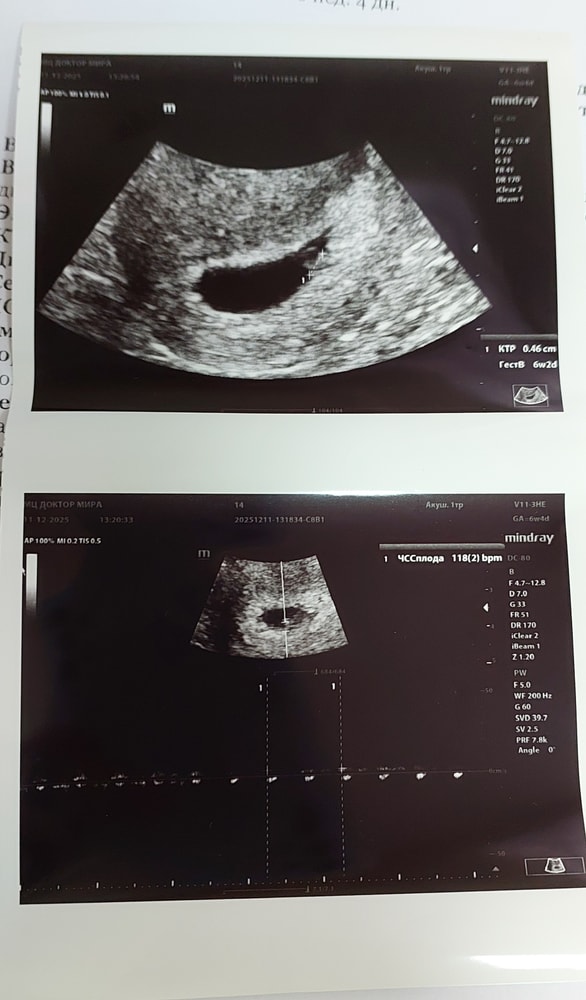

28 ДПП. 6+5 нед. УЗИ ❤️

СВД - 18,5 мм

КТР - 4,6 мм

ЧСС - 118 уд. в мин

Желточный мешочек - 3,2 мм